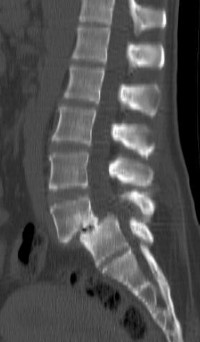

Pathologie dégénérative lombaire, Sciatiques et Cruralgies

Généralités

Spondylolisthesis lombaire